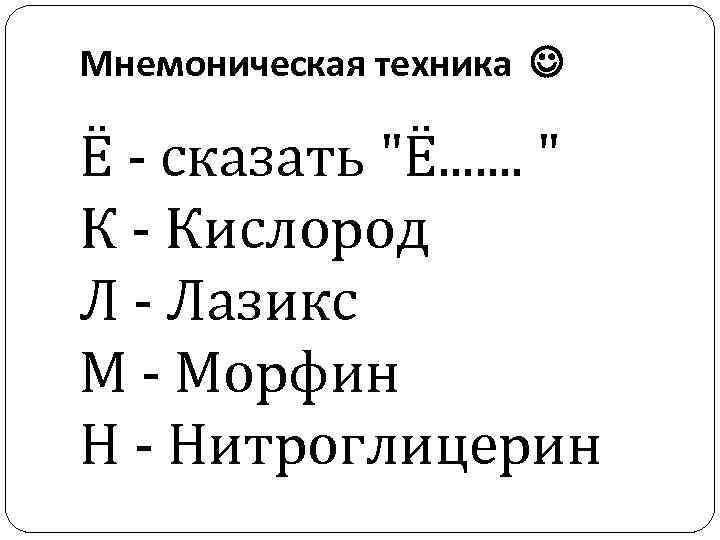

Мнемоническая техника Ё - сказать "Ё. . . . " К - Кислород Л - Лазикс М - Морфин Н - Нитроглицерин

Мнемоническая техника Ё - сказать "Ё. . . . " К - Кислород Л - Лазикс М - Морфин Н - Нитроглицерин